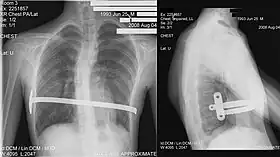

![]() X-Ray of a 15-year-old male after undergoing the procedure | |